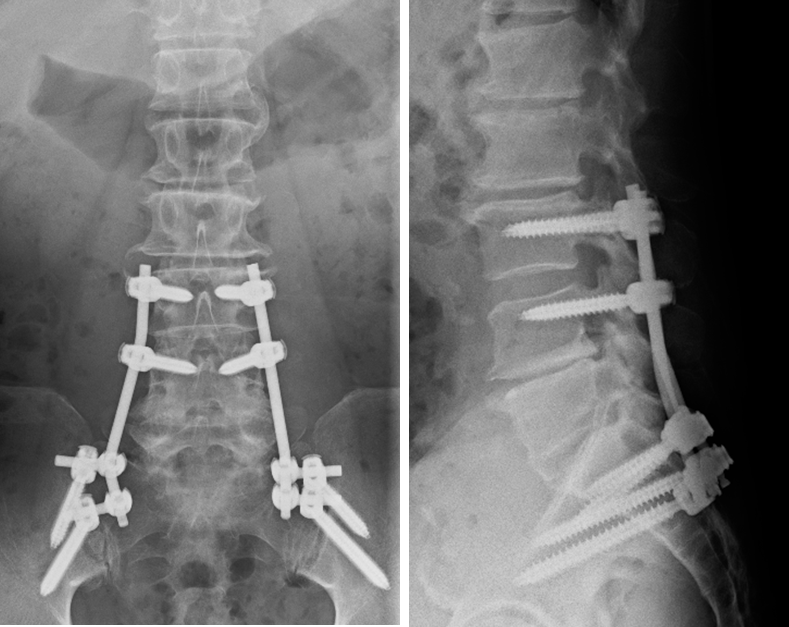

胸椎脱臼骨折を認めますが、両下肢筋力低下がなかったため、体位変換や術中操作による脊髄損傷が危惧されましたが、術中脊髄モニタリングを駆使し慎重に手術を行いました。

術後麻痺なく独歩可能です。

頚椎脱臼骨折を認めるが、四肢の筋力低下

は認めなかった。術中脊髄モニタリングを駆使し

慎重に手術を行いました。術後麻痺なく独歩可能です。